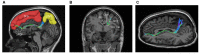

The existence of the superior fronto-occipital fasciculus (SFOF) in the human brain remains controversial. The aim of the present study was to clarify the existence, course, and terminations of the SFOF. High angular diffusion spectrum imaging (DSI) analysis was performed on six healthy adults and on a template of 842 subjects from the Human Connectome Project. To verify tractography results, we performed fiber microdissections of four post-mortem human brains. Based on DSI tractography, we reconstructed the SFOF in the subjects and the template from the Human Connectome Project that originated from the rostral and medial parts of the superior and middle frontal gyri. By tractography, we found that the fibers formed a compact fascicle at the level of the anterior horn of the lateral ventricle coursing above the head of caudate nucleus, medial to the corona radiate and under the corpus callosum (CC), and terminated at the parietal region via the lower part of the caudate nucleus. We consider that this fiber bundle observed by tractography is the SFOF, although it terminates mainly at the parietal region, rather than occipital lobe. By contrast, we were unable to identify a fiber bundle corresponding to the SFOF in our fiber dissection study. Although we did not provide definite evidence of the SFOF in the human brain, these findings may be useful for future studies in this field.